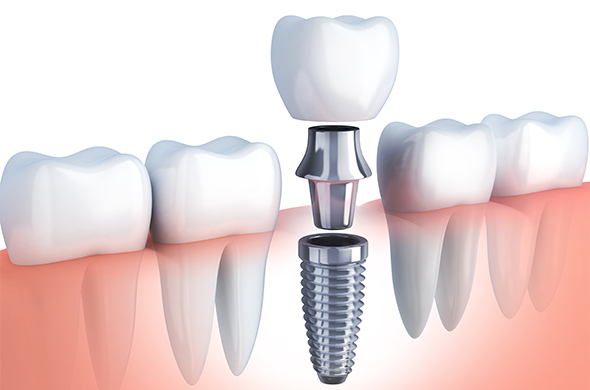

インプラント

自由診療

自分の歯のような噛み心地を取り戻したい

自分の歯のような噛み心地を取り戻したい 機能も見た目も優れた義歯にしたい

機能も見た目も優れた義歯にしたい 入れ歯が合わない

入れ歯が合わない ブリッジで歯を削りたくない

ブリッジで歯を削りたくない

インプラントとは、まるで本物の歯のような機能・見た目を持った義歯です。歯を失った部分の顎の骨に人工の歯根を埋め込み、その上に人工の歯を装着するため、ブリッジのように周りの歯を削ったり、入れ歯のようにずれたりする心配もありません。適切なメンテナンスを行えば他の義歯治療に比べて長く使用できますので、ご興味のある方はご相談ください。

当院では、インプラント治療の基礎知識を持つインプラントコーディネーターが患者さまに寄り添ってしっかりご説明しますので、安心して治療に臨んでいただけます。

※自由診療です。

※定期的なメンテナンスが必要です。